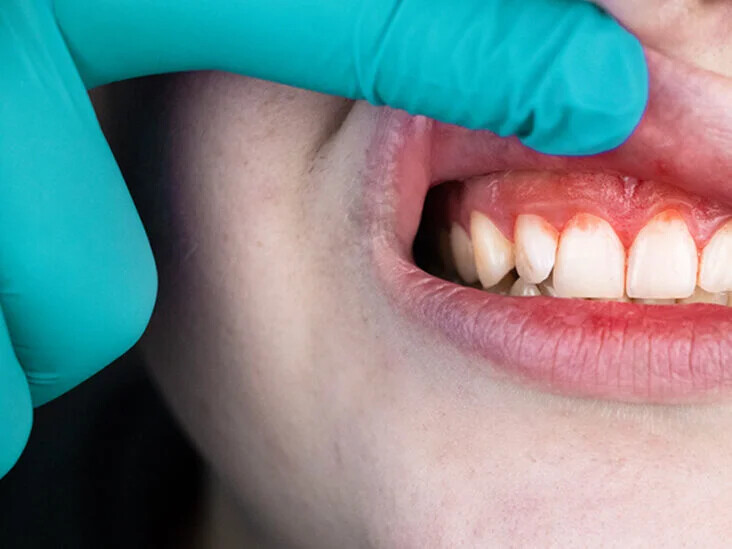

What Causes a Swollen Gum around One Tooth?

When brushing your teeth in front of the mirror, it's common to suddenly spot something you hadn't noticed before. For example, how could a swollen gum form around one tooth? And is there anything you can do about it? There are a few reasons why your gums can swell in one area, including an abscessed tooth, gum disease and improper brushing or flossing. Here are some causes of this common problem and what to do if it happens to you.

1. Hygienic Mishaps

If there is swelling around just one tooth in your mouth, it may be because you didn't brush or floss correctly, leaving behind food debris that cause tooth cavities and inflammation in the neglected area. Over time, such inadequate oral hygiene can also lead to gum disease. Be on the lookout for pale, red or swollen gums, as well as bleeding while brushing, pus coming from the tooth, a loose tooth, or persistent bad breath and taste.

2. Gum Disease

A common trigger of a swollen gum around one tooth, gum disease is a prevalent condition for which you should be on guard each time you brush. In its earliest stages, the condition's symptoms show up as red and swollen gums that, although painless, might still bleed. As the disease progresses, it can cause loose teeth due to gums that have pulled away in certain spots.

3. Abscessed Tooth

An abscessed tooth is another very common cause of local gum swelling and indicates an infection in or around your tooth. This can often come from an untreated cavity that causes germs to spread through and infect your tooth. Keep in mind that an abscess can cause irritation and ultimately cost you the tooth if left untreated. Telltale signs include throbbing pain, red or swollen gums, a swollen jaw or face, a tender or sore tooth, a fever, and even a salty taste in your mouth. Because treatment is required for an abscessed tooth, your dentist may give you antibiotics for the infection, a root canal to remove the infected pulp, or extract the tooth entirely depending on the severity.

How to Prevent Swollen Gums

It's not enough to just brush your teeth twice a day; flossing in between your teeth and using an effective mouthrinse are just as important. In addition, make sure you're brushing, flossing and rinsing with proper tools and the right technique. If you have a large space between two teeth, for instance, an interdental brush can help clean in between them. Of course, you should be going for your dental check-ups twice a year so your dentist can check not only the overall health of your teeth, but also whether your gums have receded or started to swell.

A healthy mouth and beautiful smile depend on how much care you put into both your teeth and gums. Start with oral care at home and follow it up with semiannual dental appointments to make sure your mouth health is uninterrupted from ear to ear.